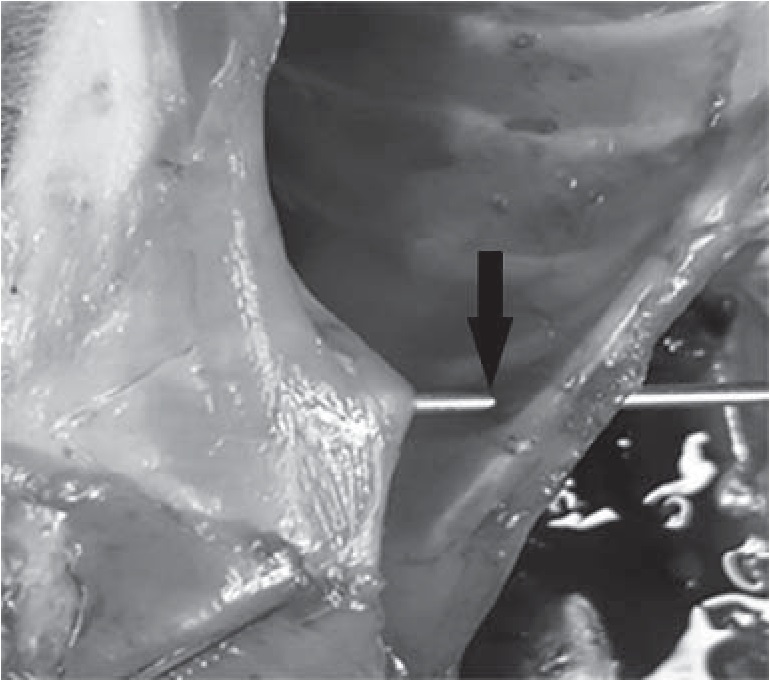

Операционное поле обрабатывалось антисептическим раствором по Филончикову – Гроссиху [1]. Пальпаторно определялся мечевидный отросток и край правой реберной дуги. При помощи скальпеля с градуированной линейкой откладывался интервал 2 см от нижнего края мечевидного отростка в сторону правой области грудной клетки. Полученная точка D соответствовала месту прикрепления диафрагмы к грудной клетке (рис. 2).

Рис. 2. Определение точки D (стрелка)

Используя точку Р, мы исключали вероятность повреждения диафрагмы (рис. 4). При помощи троакара размером 1,6 мм в сагиттальной плоскости, проходящей через точку Р под углом 45 градусов в направлении к нижнему краю мечевидного отростка, осуществляли прокол на глубину приблизительно 3–5 мм (до ощущения провала в брюшинную полость). Данная манипуляция выполнялась с целью подготовки канала для прохождения по нему пункционной иглы. Точка прокола печени представлена на рисунке 5.

Рис. 4. Исключение вероятности повреждения диафрагмы (стрелка)